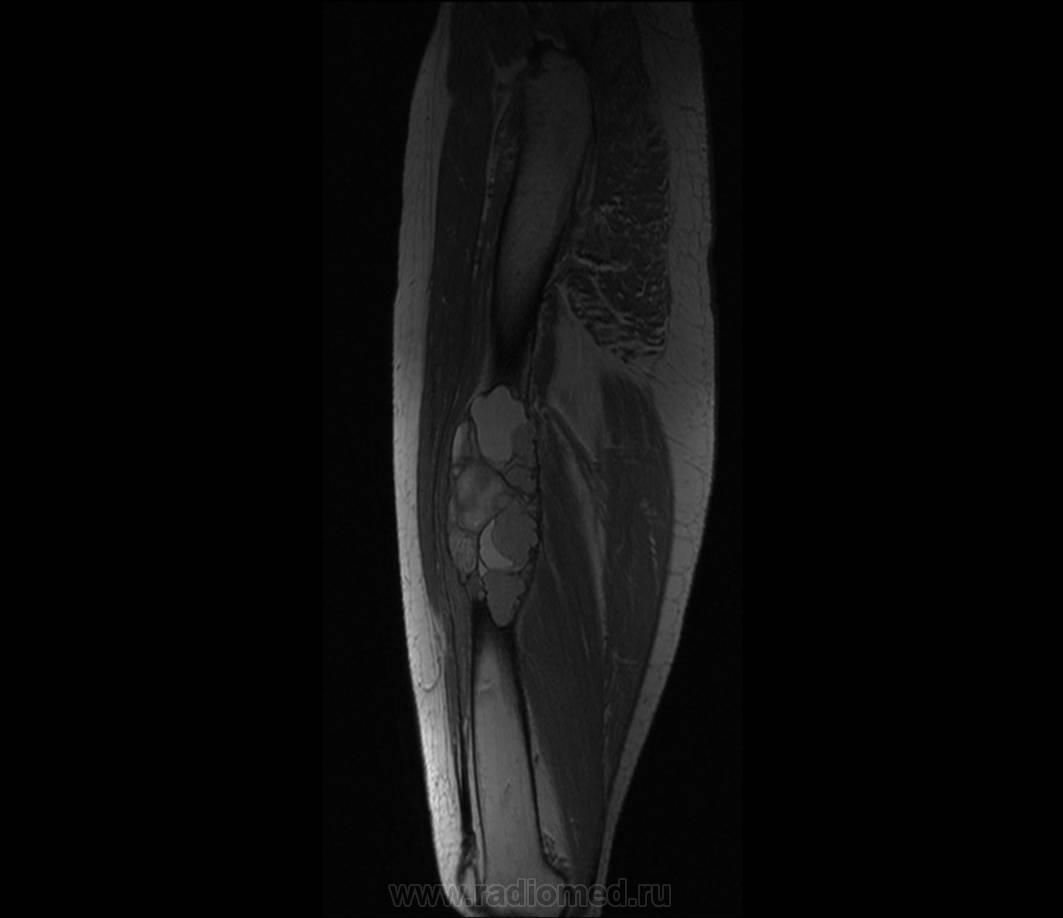

Девочка 9 лет. Родители отмечают, что 2 месяца назад девочка начала предъявлять жалобы на боли в правой пятке. Обследовались, патологии в стопе не нашли. Ребёнок постепенно начал хромать. А несколько дней назад обнаружили припухлость в в/3 бедра. Болей в бедре нет, как ночных, так и дневных. Температура не повышалась. Обратились за помощью - выполнены рентгенограммы, затем - КТ.

Злокачественная опухоль - виден луковичный периостит, инвазивный рост с лизисом кости. Но какая? Вроде бы растет из костного канала. Остеосаркома? Юинг? для этих опухолей структура какая-то больно хрящевая, мягкотканная. Хондросаркома? В таком возрасте? Почему нет клиники злокачественной опухоли кости, прежде всего - болей?

Коллеги, давайте правильно применять термины. Периостит - окончание воспаления, применяется при остеомиелите. При опухоли - периостоз - окончание избытка, продуктивного процесса. Здесь есть "козырек Кодмена", спикулообразный периостоз, но есть так же луковичный (слоистый) периостоз, который хорошо виден на отдельных КТ-срезах. Другое дело, что для диф. диагноза опухоли (то что процесс агрессивный - сомнений не вызывыает) это, по большому счету, ничего не дает. Однако, обратите внимание на вздутие. Считаю возможны варианты телеангиоэктатической или гигантоклеточной остеосаркомы. Так же не считаю возможным исключить саркому Юинга.

Да, рентгенкартина неоднозначна, конечно, в первую очередь надо исключать зло (Юинга, остеогенную), но не уверена на 100%, что это они, спикул нет, есть луковичный периостит ниже основного очага, но это не критерий злокачественности, вздутие. Был бы возраст помладше, в первую очередь подумала бы о гистиоцитозе или туберкулезе. Еще мысли об аневризмальной кисте и ГКО. Очень хочется узнать результаты гистологии.

+ Не потому ,что не согласен с остальными,просто не хочется девчонке "зла " ,а ,кстати на аксиальном срезе -горизонтальные уровни есть ,или это мне кажется ?-Если есть -тогда может быть и впрямь АКК?

Вы правы, коллега, мне тоже видятся уровни. Но если АКК, откуда периостоз? По КТ его оспорить сложно... По скиалогии, локализации наиболее подходит гигантоклеточная опухоль, тем более, что она часто сочетается с вторичной аневризмальной кистой. Но возраст?! хотя, чего сейчас только не бывает...

На операции: прошли фасцию, внешне неизменённые мышцы, обнаружили желтоватую "капсулу" опухоли, после рассечения которой в рану фонтанчиком вылилось около 100 мл гемолизированной крови, а потом разом выкровило около 300 мл свежей. Т.е., как такового мягкотканного компонента опухоли просто не оказалось! Дошли до кости, обнаружили кровоточащий сосуд в канале ближе к шейке бедра. Осуществили гемостаз, на гистологию взяли кусочки "капсулы" и кусочек кости.

Чувства смешанные - с одной стороны, появилась немаленькая надежда на доброкачественность процесса. С другой - неужели АКК и ГКО могут ТАК выглядеть???